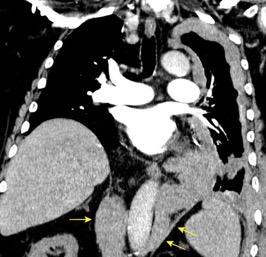

Síndrome de afectación postcardiaca (postcardiac injury)

Post infarto 1-7 % (Dressler)

Trauma cerrado Implantación marcapasos

Cirugía cardiaca. 17-31% (Post.pericardiotomía)

3707 pacientes 29 Derrames (0,78%) > de 25% del hemitórax

Todas menos 2 Izdos.

Angioplastia

By-pass coronario 21-10-03